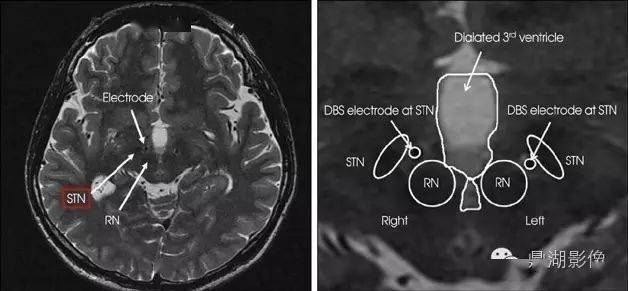

经红核黑质断面

红核与黑质的解剖要点